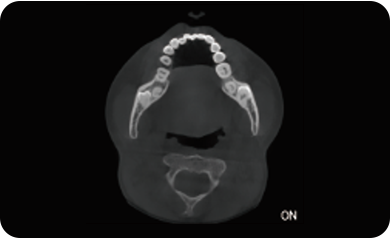

超能去伪 至臻影像

局部超清显示、 移动视野摄片

真人正侧位投影,实现CT成像区域无极可调

可根据临床需求任意调整成像区域大小实现局部超清三维显示

可根据临床需求任意调整成像区域大小实现局部超清三维显示

临床样片